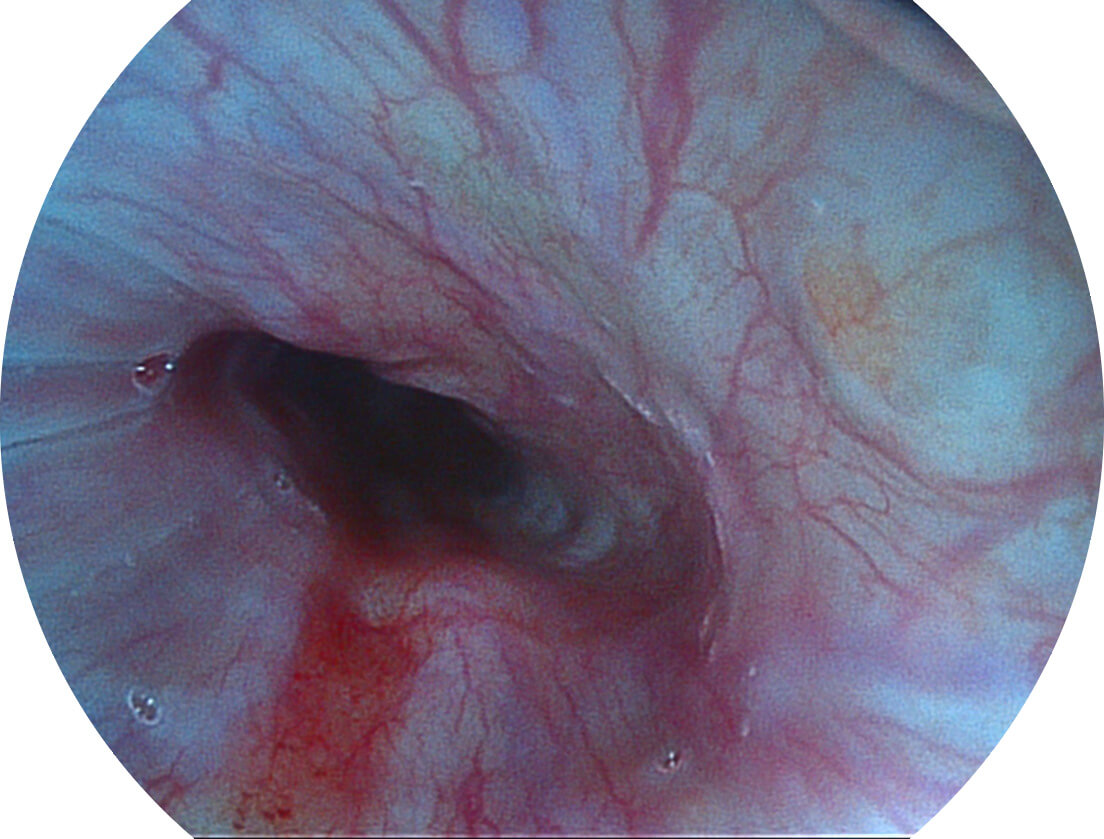

Versatile Intelligent Staining Technology, VIST

强调浅层黏膜结构的同时,保证照明亮度和提升浅层微血管与中层血管颜色对比度,病变边界更清晰。

VIST图像